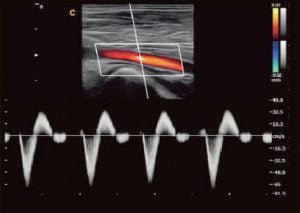

Imágenes Generales

Imágenes Cardiológicas